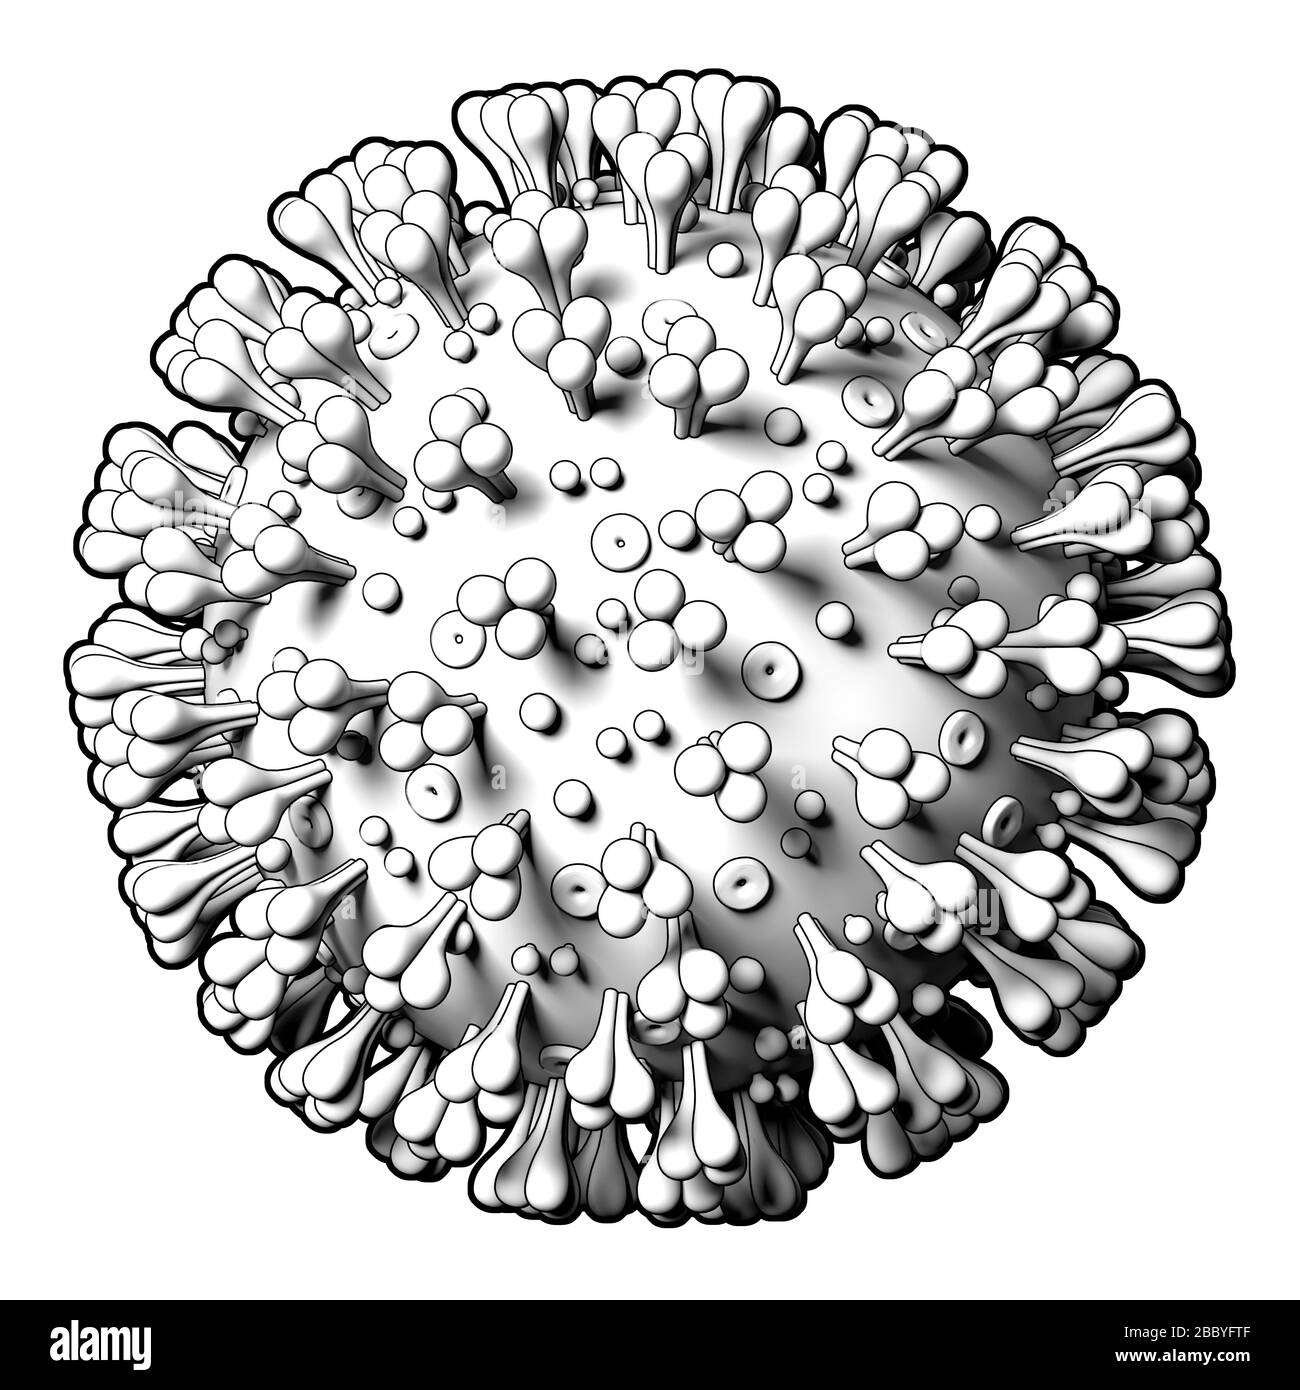

Coronavirus Covid19 modèle de virus sur fond blanc. Modèle graphique stylisé, schéma. Gros plan Banque D'Imageshttps://www.alamyimages.fr/image-license-details/?v=1https://www.alamyimages.fr/coronavirus-covid19-modele-de-virus-sur-fond-blanc-modele-graphique-stylise-schema-gros-plan-image351573727.html

Coronavirus Covid19 modèle de virus sur fond blanc. Modèle graphique stylisé, schéma. Gros plan Banque D'Imageshttps://www.alamyimages.fr/image-license-details/?v=1https://www.alamyimages.fr/coronavirus-covid19-modele-de-virus-sur-fond-blanc-modele-graphique-stylise-schema-gros-plan-image351573727.htmlRM2BBYFTF–Coronavirus Covid19 modèle de virus sur fond blanc. Modèle graphique stylisé, schéma. Gros plan